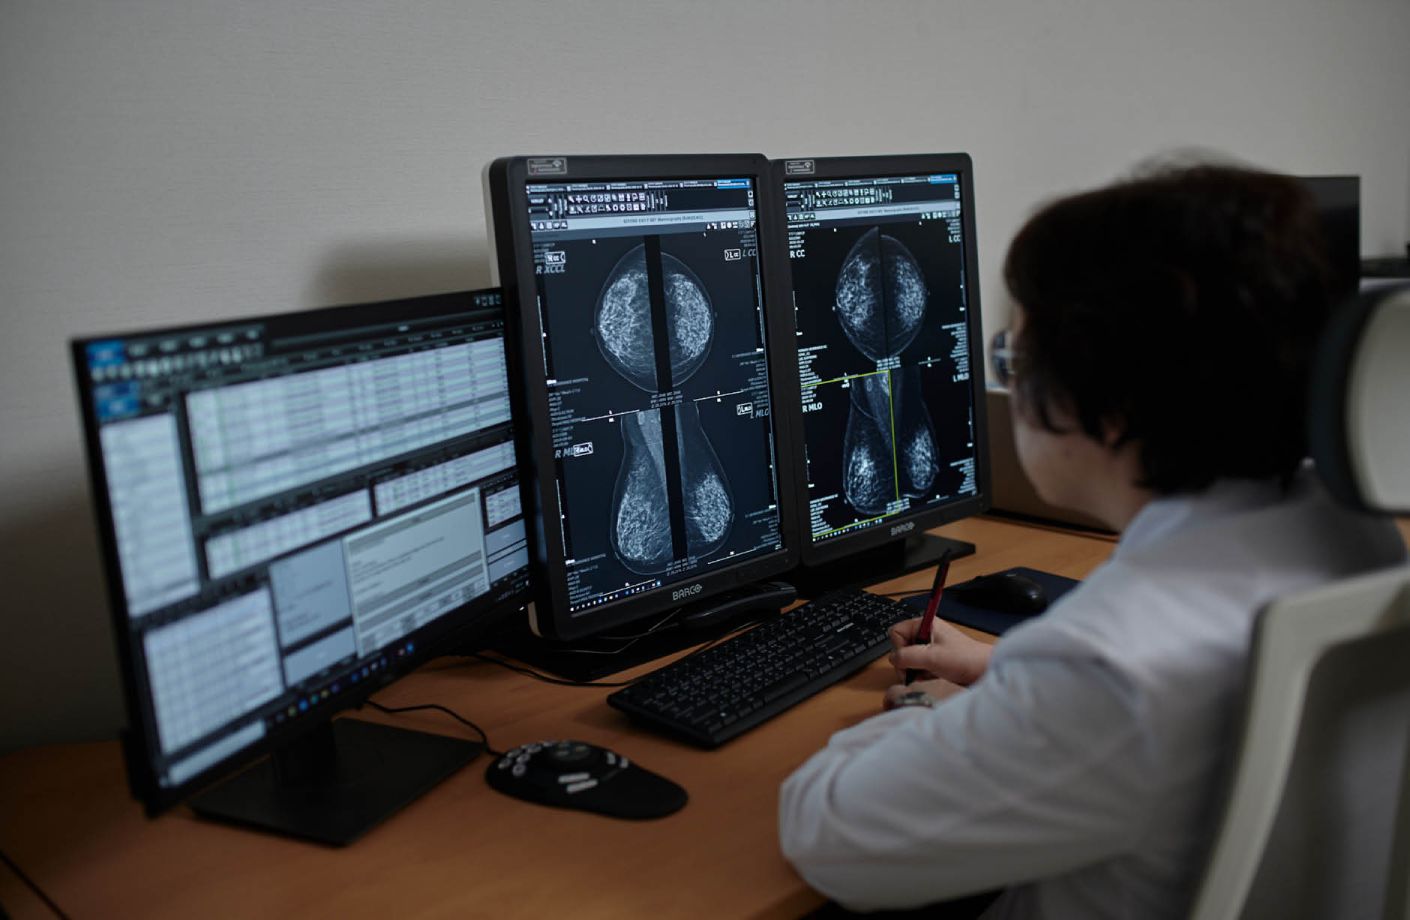

From mammograms to chest X-rays, Lunit’s technology enhances diagnostic confidence and consistency in the most diverse clinical environments.

Our partner-first approach enables rapid, secure, and stable integration of Lunit’s AI solutions into the existing radiology environments.

With flexible deployment options and dedicated technical support, Lunit’s AI fits naturally into clinical workflows—without any disruption.